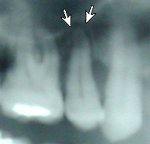

An abscessed tooth is usually sensitive or painful. The discomfort is what normally alerts the patient to the problem. Occasionally, an abscess may be detected on an x-ray and treated before the patient experiences any discomfort. Left untreated, an abscess may compromise the immune system and in some cases may become life-threatening.

x-ray